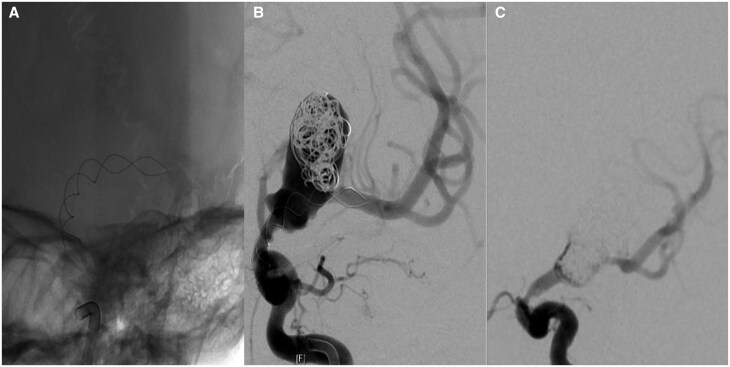

A 28-mm diameter and partially thrombosed intracranial aneurysm was found in a 10-year-old boy on an MRI for non-specific headaches. The large neck incorporated the left internal carotid artery (ICA) termination and proximal middle cerebral artery. Treatment was planned to prevent further growth and rupture. Because of the difficult anatomy, a braided stent was first placed across the aneurysm neck as a scaffold to allow for the placement of a flow-diverting stent after its endothelialisation. However, severe stent-induced endothelial hyperplasia was encountered when the flow diverter was inserted. This resulted in a transient ICA occlusion during the procedure before flow was restored by angioplasty. As a result, the patient suffered a mild transient dysphasia but permanent loss of vision in the left eye. All antiplatelet medications were stopped 1 year after the procedure without problem. The aneurysm has remained fully occluded in the 7 years since.